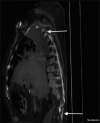

Post-operative pain after minimally invasive video-assisted thoracoscopic surgery (VATS) in adults is commonly managed with oral and parenteral opioids and invasive regional techniques such as thoracic epidural blockade. Emerging research has shown that the novel erector spinae plane (ESP) block, can be employed as a simple and safe alternative analgesic technique for acute post-surgical, post-traumatic and chronic neuropathic thoracic pain in adults. We illustrate this by presenting a paediatric case of VATS, in which an ESP block provided better analgesia, due to greater dermatomal coverage, as well as reduced side-effects when compared with a thoracic epidural that had previously been employed on the same patient for a similar procedure on the opposite side.